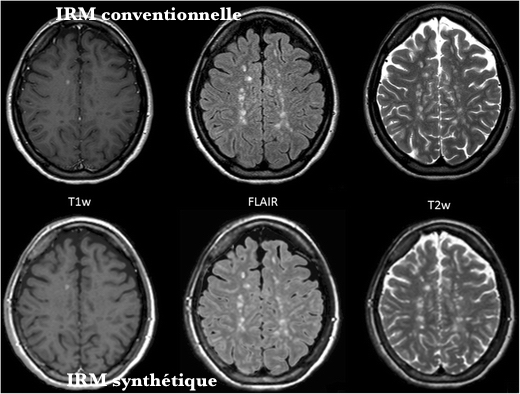

Les images synthétiques d'IRM sont calculées par des algorithmes afin d'obtenir des contrastes d'image analogues aux pondérations T1 et T2 classiques (T1W et T2W) et FLAIR. Elles sont obtenues à partir d'une seule acquisition par rapport à l'imagerie conventionnelle où les séries de contraste d'image sont obtenues une par une.

Une étude publiée en ligne dans l'European Journal of Radiology se propose de comparer ces images synthétiques à celles obtenues par des séquences IRM classique dans l'exploration de la Sclérose en Plaques (SEP). Des études précédentes d'IRM synthétique reproduisant les images conventionnelles T1W, T2W et FLAIR ont montré que les images de T1W et T2W sont comparables mais que les images FLAIR calculées synthétiquement ont une qualité inférieure à celle des images d'IRM conventionnelles.

Des images axiales synthétiques et conventionnelles ont été acquises prospectivement pour 52 patients atteints de SEP diagnostiquée. L'IRM quantitative (qMRI) a été utilisée pour mesurer la densité de protons et les temps de relaxation (T1, T2) puis, sur la base de ces paramètres, des images synthétiques T1W, T2W et FLAIR ont été calculées. Les séries d'images ont été examinées à l'aveugle, indépendamment et dans un ordre aléatoire par deux radiologues. Le nombre et l'emplacement de toutes les lésions ont été documentés et catégorisés. Un rapport combiné de la charge de la lésion et de la présence de lésions rehaussant le contraste a été compilé pour chaque patient.

Dans cette population souffrant de SEP, 13 patients présentaient des lésions de la substance blanche. Au total, 260 piles d'images ont été examinées par les deux évaluateurs. Ces derniers n'ont pas identifié de différences significatives dans le nombre de lésions entre l'IRM conventionnelle et synthétique pour les trois types d'images (T1, T2, FLAIR). La détection des lésions a montré des résultats similaires pour les images conventionnelles et synthétiques.

En conclusion, les images IRM synthétiques ont le potentiel d'être utilisées dans l'évaluation de la dissémination de la SEP dans l'espace malgré d'infimes caractéristiques plus faibles par rapport aux images d'IRM conventionnelles. Des études évaluant l'impact de ces différences sur la prise en charge clinique et l'IRM synthétique dans l'évaluation de la dissémination des lésions de SEP au cours du temps restent à effectuer.